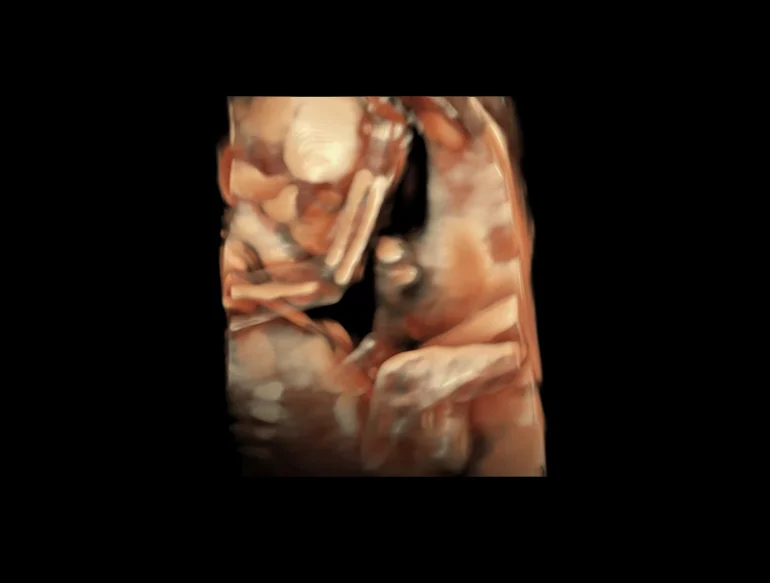

Откройте для себя уникальные возможности визуализации, позволяющие с легкостью обнаруживать тонкие анатомические структуры в 2D-, 3D- и 4D-режиме.

8-недельный эмбрион (технология HDlive Studio)

Трехмерный режим — дальнейшее развитие В-режима. Объемное трехмерное изображение достигается путем компьютерного преобразования сигнала, полученного при помощи датчика с изменяющейся плоскостью излучения. Данный метод позволяет получить объемное изображение органа и исследовать его в различных проекциях. Особенно информативным он оказался в пренатальной диагностике врожденных аномалий развития плода. В ультразвуковых приборах экспертного и высокого классов имеется режим трехмерной энергетической доплерографии или трехмерной ультразвуковой ангиографии. Прибором реконструируется трехмерное изображение только цветовой части эхограммы, характеризующей кровоток в сосудах. Меняя ракурс наблюдения, поворачивая трехмерное изображение сосудов, получают представление о пространственном расположении и форме сосудов, что дает дополнительную диагностическую информацию.